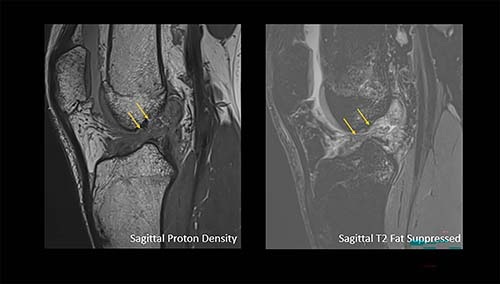

Finally, Sutter reviewed a number of possible clinical implementation directions for 7-tesla MRI, describing how it improved treatment planning in a 52-year-old woman involved in a skiing accident: 1.5-tesla MRI showed an anterior cruciate ligament (ACL) tear and a nondisplaced fracture of the tibial head, and she was referred for conservative treatment. However, 7-tesla MRI revealed a more complex tear and a meniscal ramp lesion, which directed her to surgery. In another case, 7-tesla MRI identified delamination of femoral cartilage in a 41-year-old male snowboarder that 1.5-tesla MRI missed.

Direct comparison of the ACL with 7T and 3T. Image courtesy of Dr. Reto Sutter."[Studies have shown] that 7T MRI has higher diagnostic accuracy when it comes to visualizing low-grade meniscus and cartilage damage, and that [the technology] can be superior to 3T MRI for detecting small calcifications in articular cartilage and menisci," he said.